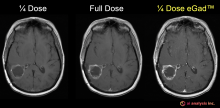

VIDEO: Artificial Intelligence May Help Reduce Gadolinium Dose in MRI